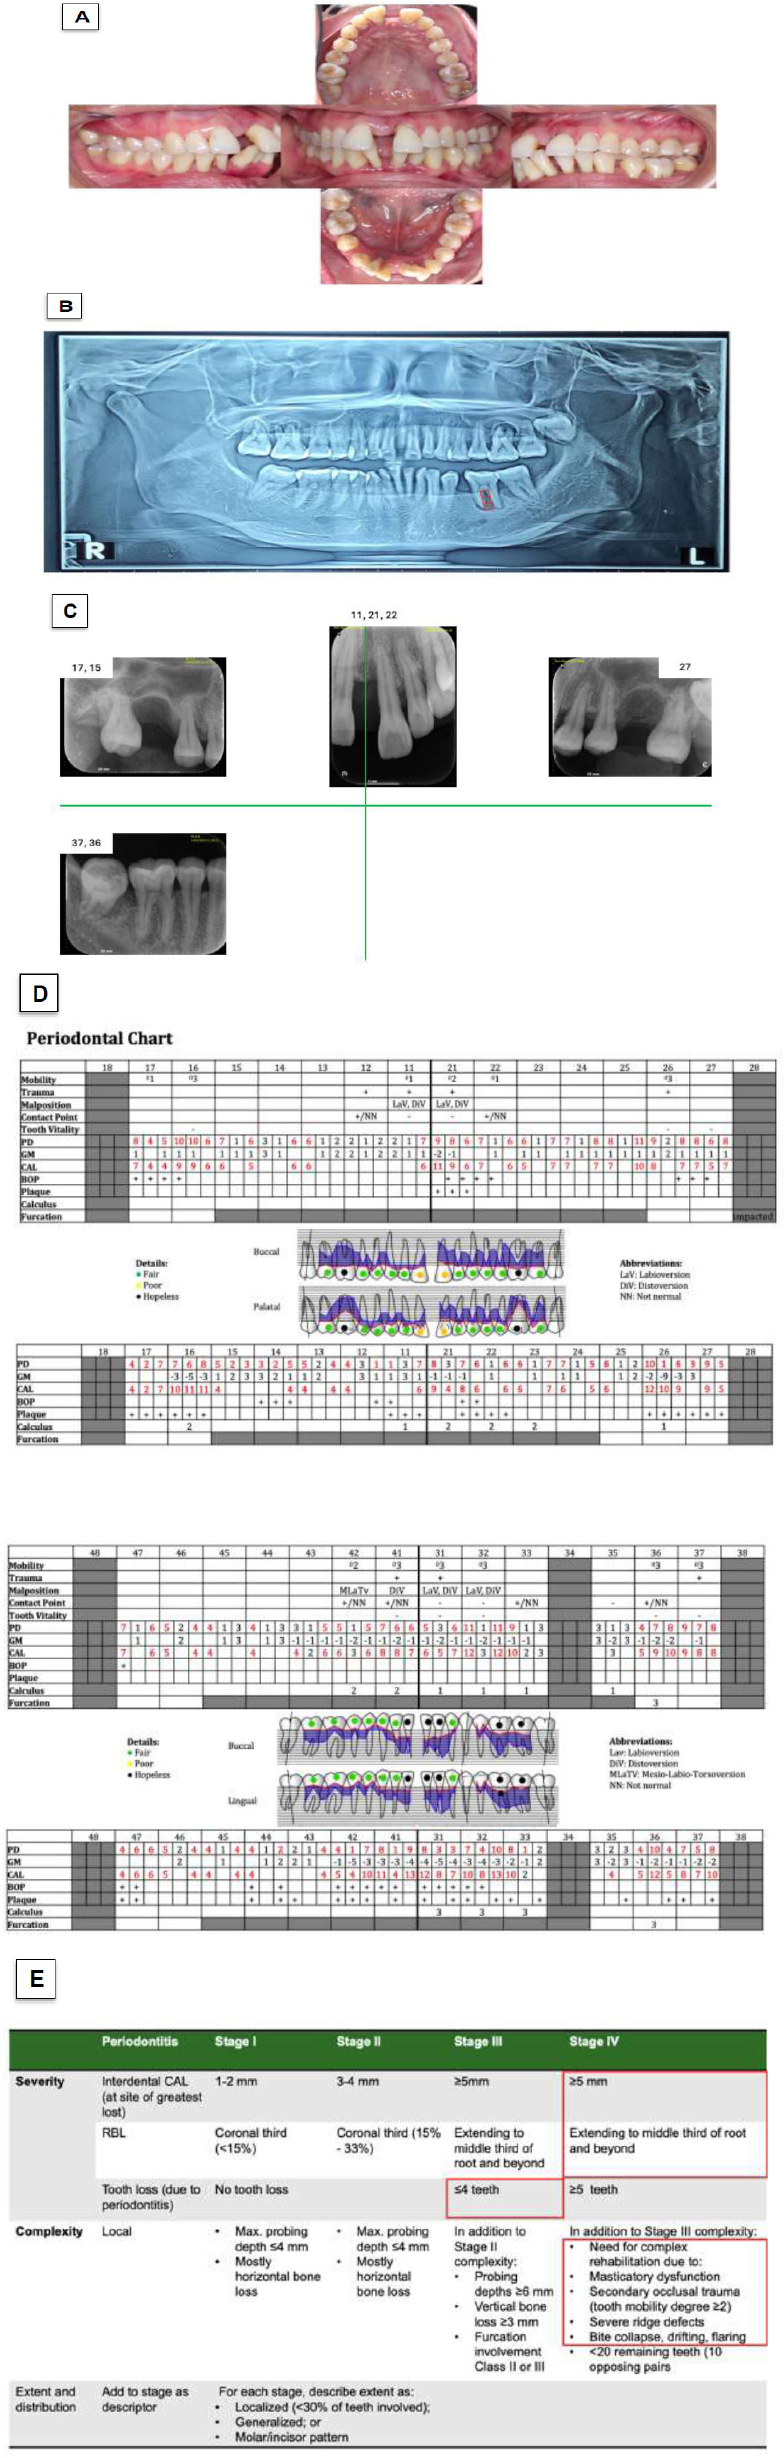

The clinical examination revealed a plaque score of 37% and bleeding on probing (BoP) of 36%, indicating active periodontal inflammation. The patient exhibited flaring of the anterior maxillary and mandibular teeth, accompanied by central diastemas in both arches. Teeth 16, 26, 31, 32, 41, 42, 36, and 37 demonstrated second- to third-degree tooth mobility (Fig. 1A-E). Tooth 34 was missing, and class II furcation involvement was present on tooth 36. The clinical attachment loss (CAL) ranged from 2 to 13 mm (Fig. 1A and D). The radiographic bone loss extended from the mid-third to the apical-third of the root, with vertical bone loss reaching the mid-third of the root of tooth 47. In addition, teeth 16, 26, and 36 showed radiolucency in their apical regions (Fig. 1B and C).

The severity factor for staging this case was determined by the greatest loss of interdental CAL and radiographic bone loss. This case was classified as stage IV due to the greatest interdental CAL of 13 mm at tooth 32 and radiographic bone loss reaching the mid-third of the root and beyond. Additionally, based on the complexity factors, this case exhibits nearly all indicators of the need for complex rehabilitation, such as flaring, drifting, masticatory dysfunction, and secondary occlusal trauma. Regarding the extent of the disease, the data suggested a likely molar-incisor pattern, as these teeth were the most severely affected. The pathological tooth migration in this case required correction through orthodontic treatment. Therefore, this case is classified as type 2 of stage IV periodontitis (Fig. 1E).

The grading of this case was primarily determined by the 100% bone loss of tooth 36 divided by the patient’s age (34 years), resulting in a ratio of 2.9. This score indicates rapid progression of periodontal destruction. However, this case did not have any grade modifiers because the patient’s HbA1C level was normal and the patient was a nonsmoker. The final diagnosis for this case is molar-incisor stage IV, grade C, type 2 periodontitis.

Case 1 clinical presentation and classification decision-making. (A) Intraoral conditions. (B) Panoramic radiograph. (C) Periapical radiographs taken after initial treatment. (D) Full-mouth periodontal chart. (E) Staging and grading criteria as established in the 2017 World Workshop.